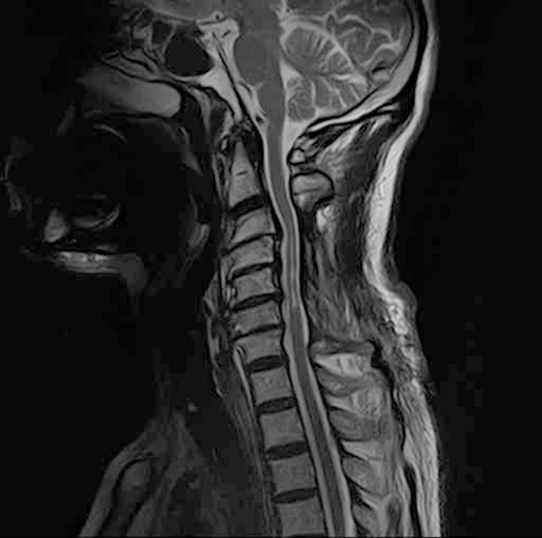

术前MRI显示,颈髓在C3-C6节段出现广泛的髓内T2高信号。由于之前椎板切除术区域存在纤维化瘢痕组织,SCS电极无法植入颈段硬膜外间隙,因此将2根电极植入T8-T11节段,并进行体外测试治疗。3周测试期间,患者疼痛明显改善,随后进行了永久植入。刺激参数为:频率10kHz,脉宽30μs,双极刺激,幅度范围0.5mA-3.5mA。